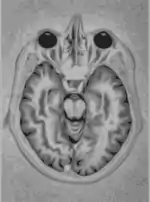

Cerebro explorado con MRI.

Un instrumento de imágenes por resonancia magnética (Scanner MRI) usa imanes de elevada potencia para polarizar y excitar núcleos de hidrógeno (protón único) en moléculas de agua en tejidos humanos, produciendo una señal detectable que está codificada espacialmente produciendo imágenes del cuerpo. Resumiendo, MRI implica el uso de tres clases de campos electromagnéticos: un campo magnético estático muy fuerte para polarizar los núcleos de hidrógeno, llamado el campo estático, de un orden de unidad de teslas; un campo variante (en el tiempo, del orden de 1 kHz) más débil para la codificación espacial, llamado el campo de gradiente; y un campo de radio-frecuencia débil para la manipulación de los núcleos de hidrógeno para producir señales medibles, recogidas mediante una antena de radio-frecuencia. Como CT, MRI crea normalmente una imagen 2D de una "rebanada" delgada del cuerpo y por tanto es considerada una técnica de imagen tomográfica.

Los instrumentos modernos de MRI son capaces de producir imágenes en forma de bloques 3D, que se pueden considerar una generalización del concepto tomográfico de la "rebanada" individual. A diferencia del CT, MRI no implica el uso de radiación ionizante y no está por tanto asociada con los mismos riesgos para la salud; por ejemplo, no hay efectos conocidos a largo plazo por la exposición a campos estáticos fuertes (esto es materia de algunos debates; vea 'Seguridad' en MRI) y por tanto no hay límite en el número de exploraciones a las que una persona puede ser expuesto, en contrates con los rayos X y CT. Sin embargo, hay asociados riesgos conocidos para la salud con el calentamiento de tejidos por la exposición a campos de radio-frecuencia y la presencia de dispositivos implantado en el cuerpo, tales como marca-pasos. Estos riesgos están estrictamente controlados tanto en la parte de diseño de los instrumentos como en los protocolos de exploración utilizados. Debido a que CT y MRI son sensibles a diferentes propiedades de los tejidos, la aparición de imágenes obtenidas con las dos técnicas difieren considerablemente. En CT, rayos X deben ser bloqueados por alguna forma de tejido denso para crear una imagen, por lo tanto la calidad de la imagen en tejidos blandos será pobre. Un MRI puede "ver" únicamente objetos basados en hidrógeno, así que los huesos, que está basados en calcio, serán anulados en la imagen, y no tendrán efectos en la visión de tejidos blandos. Esto lo hace excelente para examinar el interior del cerebro y las articulaciones.

Imagen del cerebro.

La imagen anterior es una imagen del cerebro. Es una prueba que permite el diagnóstico del trastorno de Parkinson. Se trata de una imagen tomográfica (SPECT).